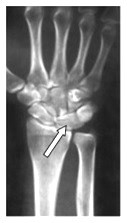

Na radiogramie uwidoczniono

Ilustracja do pytania 3

A. złamanie podstawy I kości śródstopia.

B. paluch koślawy (hallux valgus) stopy prawej.

C. paluch szpotawy(hallux varus) stopy prawej.

D. złamanie guzowatości V kości śródstopia.